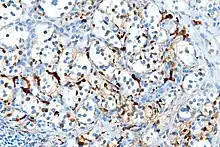

Micrograph of a carotid body tumor

On microscopic inspection, the tumor cells are readily recognized. Individual tumor cells are polygonal to oval and are arranged in distinctive cell balls, called Zellballen.[8] These cell balls are separated by fibrovascular stroma and surrounded by sustentacular cells.

By light microscopy, the differential diagnosis includes related neuroendocrine tumors, such as carcinoid tumor, neuroendocrine carcinoma, and medullary carcinoma of the thyroid.

With immunohistochemistry, the chief cells located in the cell balls are positive for chromogranin, synaptophysin, neuron specific enolase, serotonin, neurofilament and Neural cell adhesion molecule; they are S-100 protein negative. The sustentacular cells are S-100 positive and focally positive for glial fibrillary acidic protein. By histochemistry, the paraganglioma cells are argyrophilic, periodic acid Schiff negative, mucicarmine negative, and argentaffin negative.